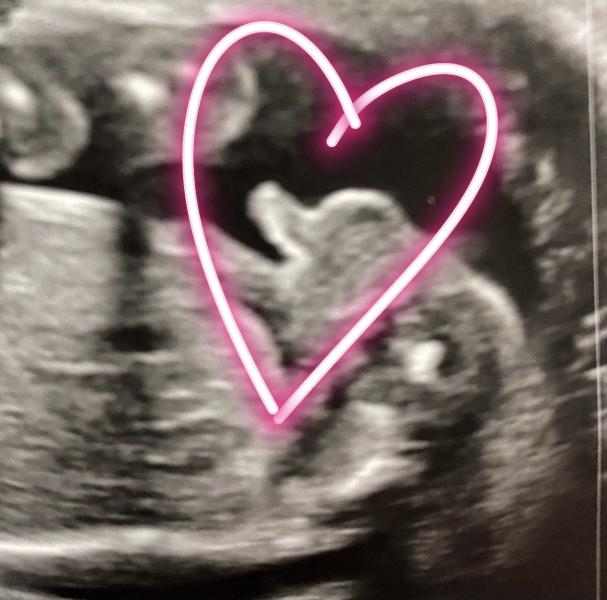

Делала сегодня второй скрининг у Глебова в «Медсонар». Подтвердил мальчика (на втором фото обведён сердечком наш писюн🤣). У малыша всё хорошо, 357 гр😅 Опережает развитие на несколько дней и поэтому пдр ставят на 2 мая, а не 6-е. Сидит на попе))